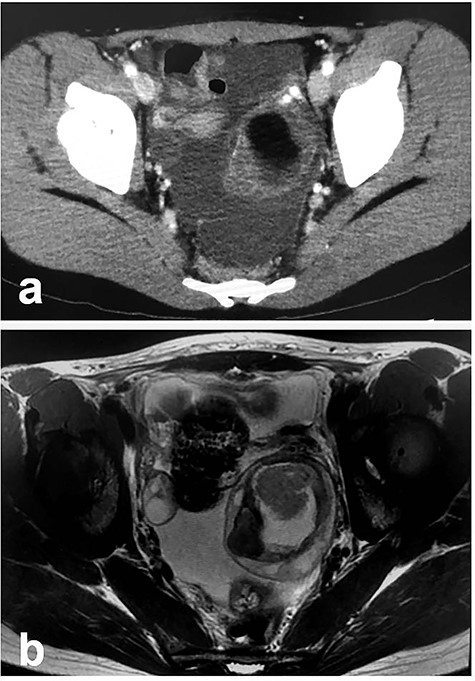

Patient 1: In a 12-year-old girl with abdominal pain, enhanced computed tomography (CT) showed a swollen appendix and a left ovarian mass; she was diagnosed with appendicitis (Fig. 1a). After laparoscopic appendectomy, she underwent magnetic resonance imaging (MRI), which revealed an ovarian MCT (38 cm × 30 cm; Fig. 1b). She underwent a second procedure, laparoscopy-assisted extracorporeal cystectomy (a hybrid, minimally invasive approach), during which the tumor was placed in a specimen retrieval bag and exteriorized through a suprapubic incision. The tumor was then excised, and the ovary returned to the pelvis. There was no content spillage (Fig. 2). The excised margins of the tumor were continuously oversewn using absorbable suture. Pathologic examination confirmed the diagnosis of MCT. The patient has been doing well without evidence of recurrence. She subsequently established a regular menstrual cycle.